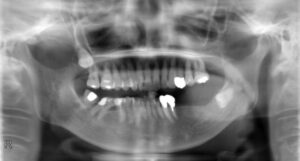

下顎臼歯3本欠損症例

BEFORE AFTER 71歳女性/下顎3本欠損/インプラント埋込手術 【治療内容】 左下には部分義歯を使用されていま…